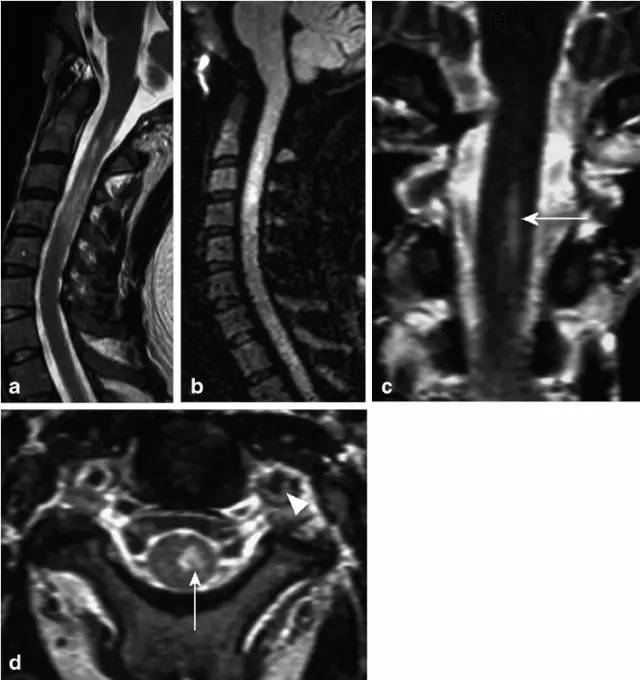

病例3:33岁女性,脊髓沟动脉综合征。矢状位T2(图a)显示颈髓不均匀高信号,DWI高信号(图b)。增强(图c)和轴位T2(d)显示左侧髓质梗死(图c,d,箭头),V2和V3水平显示左侧椎动脉夹层(图d,箭头)

病例4:桶人综合征,可疑右侧椎动脉夹层。T2(图a矢状位,图c轴位)显示脊髓前角(图c,箭头)铅笔画样(图a,箭头)髓内高信号。随访MRI(图b矢状位,图d轴位)显示C5/6水平(图b,箭头)局限性脊髓萎缩,双侧脊髓前角高信号(图d)